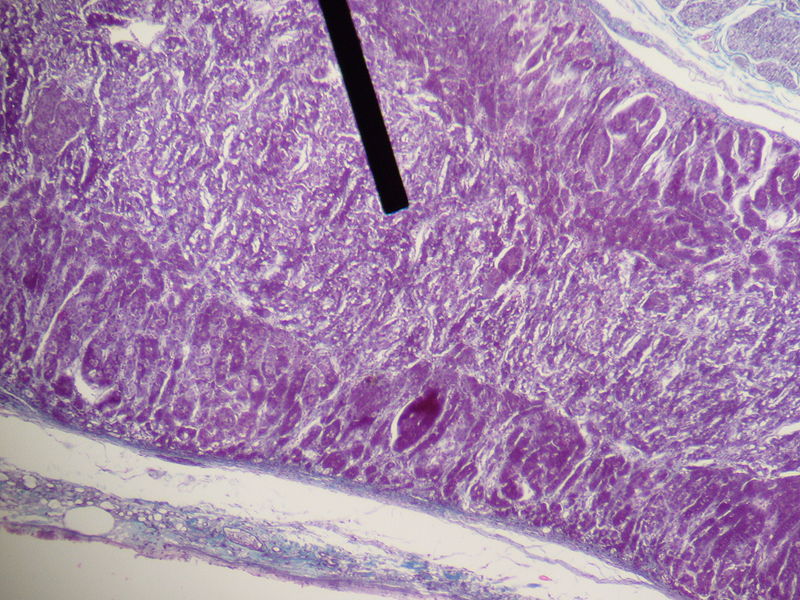

Adrenal Cortex

The largest and outermost portion of an adrenal gland is called the adrenal cortex.

The adrenal gland is composed of three distinct zones which include:

- Zona glomerulosa

- Zona fasciculata

- Zona reticularis

Zona glomerulosa produces mineralocorticoids like aldosterone.

Zona fasciculata creates glucocorticoids like cortisol.

Zona reticularis generates sex hormones like testosterone.